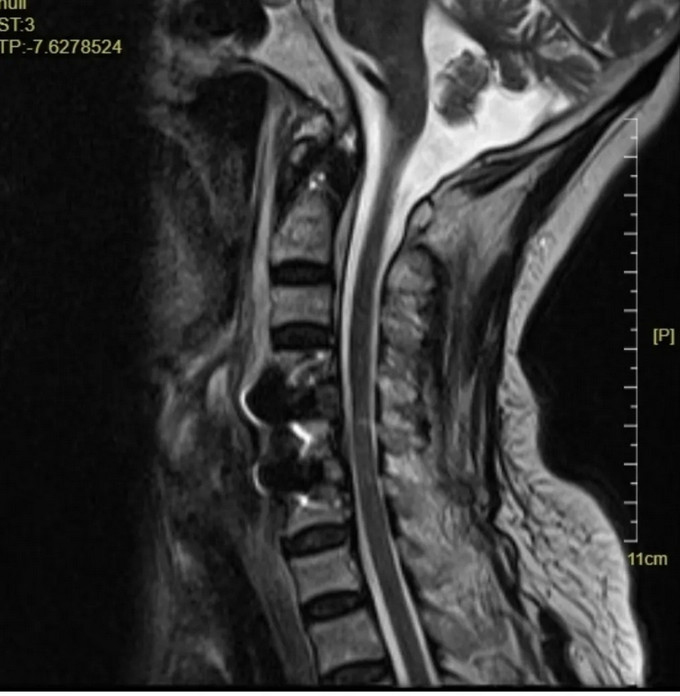

頸椎MRI矢狀位,可以看到患者的頸神經(jīng)被明顯壓迫

C4-5、C5-6椎間盤突出伴鈣化,C4-5、C5-6 層面脊髓變性。